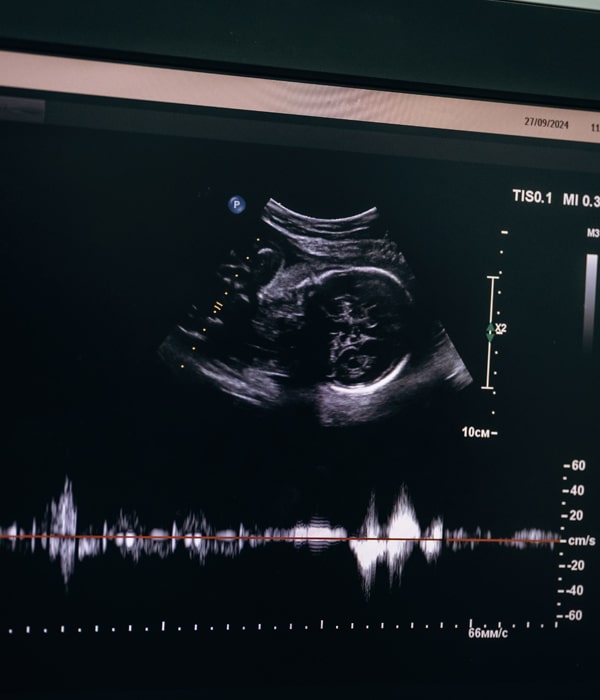

Specialized Ultrasound to Assess the Baby’s Heart During Pregnancy

Fetal echocardiography is a specialized ultrasound that focuses solely on the baby’s heart. It provides detailed imaging of:

- Heart chambers, valves, and vessels

- Heart rhythm and pumping function

- Blood flow patterns

- Position and connections of the great arteries

It is typically performed between 18 and 24 weeks, though it can be done earlier or later depending on the situation.